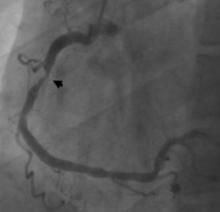

Two large clinical trials were presented in the late-breaking clinical trials session at the American College of Cardiology's (ACC) 61st Annual Scientific Session this week that indicate coronary computed tomography angiography (CCTA) used as a tool to evaluate patients with chest pain in the emergency department is safe, time-efficient and cost-effective, compared to the current standard approach.

Coronary angiography is unable to accurately predict the severity of vessel narrowing, suggesting fractional flow reserve (FFR) functional tests should be added to help determine if a patient needs revascularization. This was according to research presented from the IRIS FFR-DEFER trial at the American College of Cardiology's (ACC) 61st Annual Scientific Session this week in Chicago.